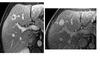

Features of pyogenic hepatic abscess?

Pyogenic -Singular - Klebsiella -Multiple - E.coli -'Double targe sign' -Confluent complex cystic lesions Candida - Bulls eye Amoebic - 'extra hepatic extension' - if left lobe needs emergently drained as can rupture into the pericardium -transient hepatic attenuation difference (THAD) due to thrombophlebitis of portal vein and hyperemia of abscess capsule - enhancing capsule and hypodense halo of edema Hydatid - 'water lily, sandstorm' - Large, well-defined, cystic liver mass with numerous peripheral daughter cysts - Echinococcus Schistosomiasis is - 'Tortoise shell' - Septations hyperdense